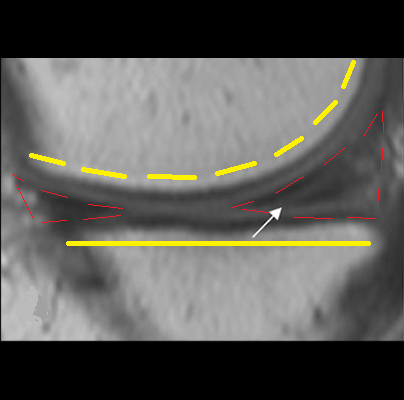

Los meniscos tienen una función biomecánica importante: su forma les permite adaptarse en la cara superior al contorno redondeado del femur y en su cara inferior se adaptan a la forma aplanada de la Tibia.

De esta manera, parte el peso que viene de la superficie esférica del fémur, se transmite hacia la tibia a traves de los meniscos, disminuyendo la presión entre ellos, con lo que se preserva el cartílago articular.